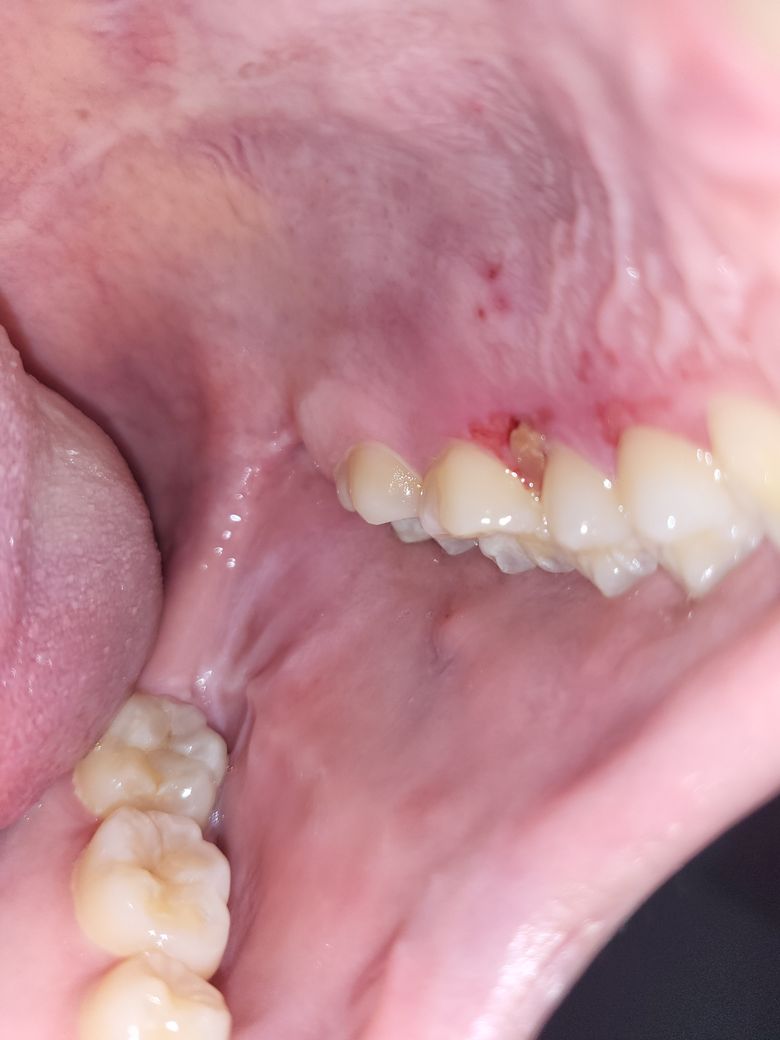

잇몸 안쪽에 딱딱한 무언가가 났어요

전에 딱딱한 뭔가가 느껴져서 치과에 가려다가 까먹고 있었는데 오늘 통증이 느껴져서 사진을 찍어봤더니 딱딱한 뭐가 있더라구요 검색해보니 염증이라는 말도 있고 외골증이라는 말도 있는데 뼈처럼 보이진 않습니다

사진에 보이시는 것처럼 잇몸에 작은 딱딱한 무언가

가 났습니다 이게 무엇인가요? 빨리 병원에 가보는게 좋을까요?

• 1번 째 사진

사진으로 약간 노랗게 보이는 것이 염증으로 보입니다. 그러나 염증은 딱딱하지는 않습니다.

딱딱하다면 무언가 잇몸에 끼어있는 것 일 수도 있습니다.

해당 부위 뿐만 아니라 같은 쪽 앞쪽 치아도 붉게 보이는 것으로 보아 구강 내 연조직 질환일 가능성이 큽니다. 즉 단순 구내염은 아닌 것으로 보여지며 해당 부위가 2주 이상 진행되었다면 반드시 치과 방문 후 감별진단을 받아보셔야 합니다. 대부분 경미한 외상이나 구내염은 2주 전후로 회복합니다. 회복하지 않을 때는 반드시 감별진단을 받아보셔야 합니다.

사진으로만 봐서는 어떤 물질인지 판단하기가 힘듭니다.

주변에 구내염 증상이 있는것으로 보아 구내염으로 보이지만 구내염일 경우에는 딱딱하지 않아요.

자세한 확인을 위해서 치과병원에서 검사를 받아 보시기를 권유드립니다.